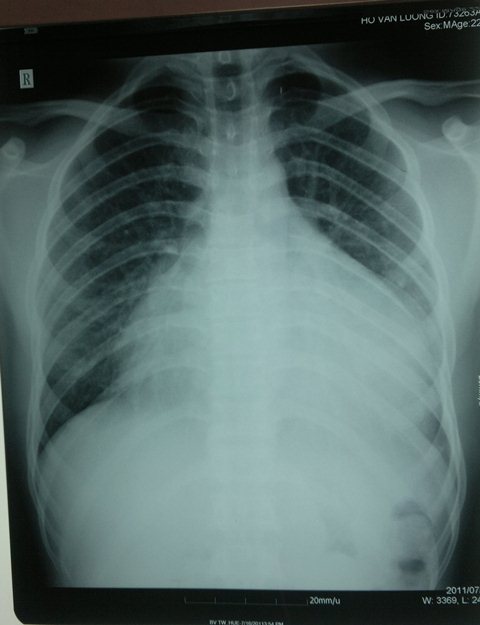

Tràn dịch màng ngoài tim